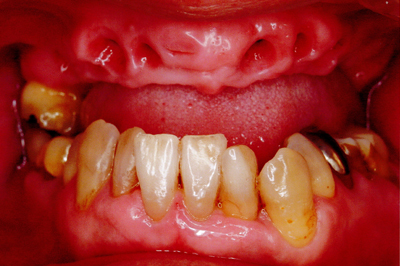

治療例1

| ご費用 | 手術費用人工歯根 1本275,000円(税込) 上部構造 88,000円~110,000円(税込) |

|---|---|

| リスク・副作用 |

保険非適応(自費診療) 特定の全身疾患や持病のある方、顎骨密度の足りない方、妊娠中の方は手術ができない場合があります。 下顎のインプラント手術の際、偶発症のリスクがあります。 人工歯根が顎骨と癒着しないリスクがあります。 インプラント周囲炎になるリスクがあります。 |